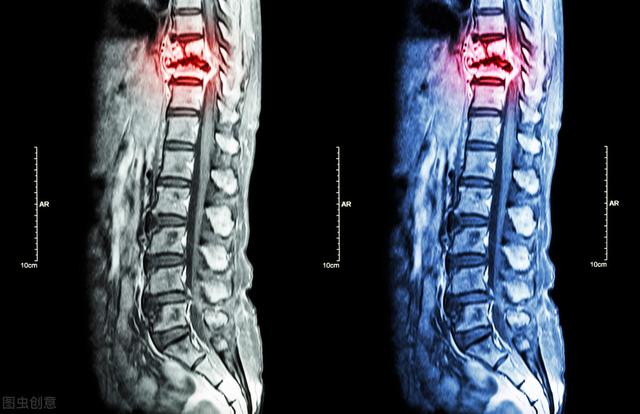

骨転移の磁気共鳴画像法

胸椎に発生した骨転移性癌を示す。